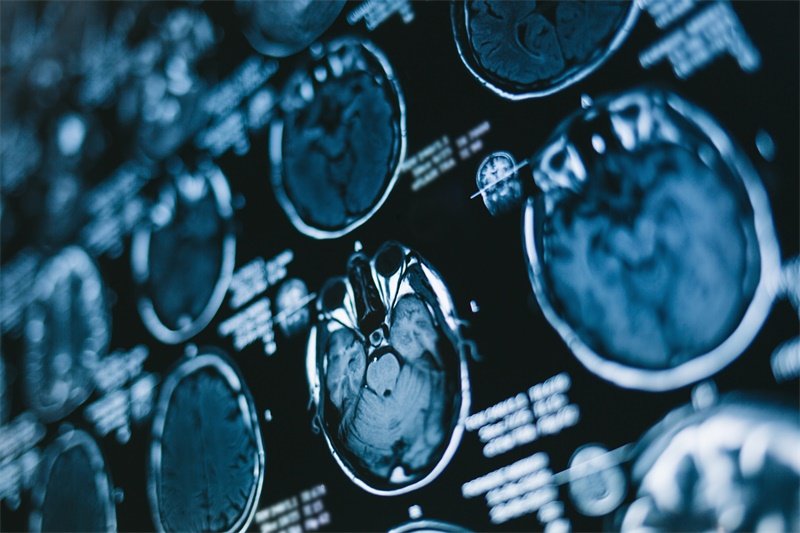

影像学检查

磁共振成像(MRI)和计算机断层扫描(CT)是最常用的检查手段。这些技术能够提供大脑结构的清晰图像,有助于医生识别CPA区域的任何病变。